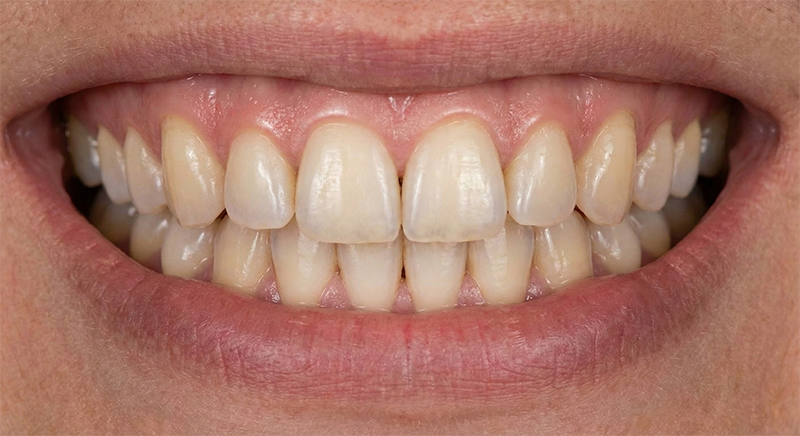

모두가 임플란트를 이야기할 때, 대학병원 보존과 출신 전문의는 살릴 수 있는 마지막 가능성을 먼저 확인합니다.

디지털아트치과가 0.1mm의 치아 삭제에도 집착하는 이유, 가장 좋은 치아는 이미 당신 입안에 있기 때문입니다.

임플란트가 아무리 좋아도

타고난 내 치아보다 좋을 수는 없습니다